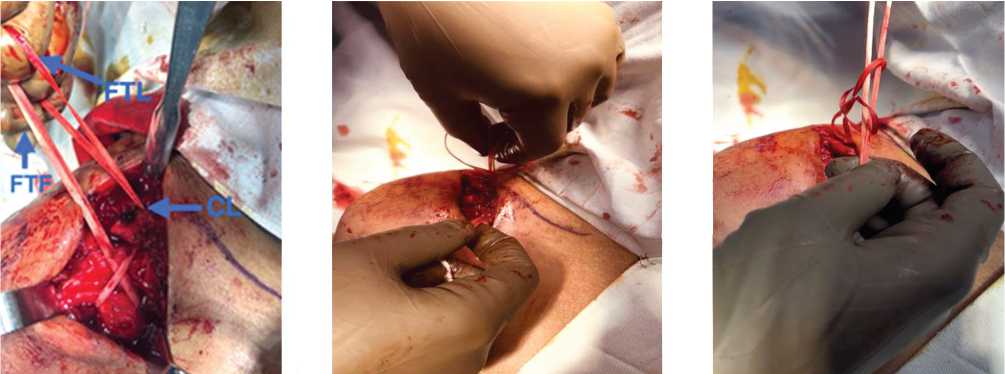

All acute Rockwood III–VI ACJ separations and lateral end clavicle fractures were considered for reconstruction. The patients were given either regional or general anesthesia, depending on the ASA grade or the anesthetist’s preference. Preoperative broad-spectrum antibiotics were administered. A beach chair position was given, and scrubbing, painting, draping, and marking done (Fig. 1). Approximately five centimeters in length, a vertical skin incision was made from the clavicle lateral end to the coracoid process tip and the coracoid process was identified (Fig. 2). From 4 cm of the lateral end of the clavicle, a 4-mm tunnel was drilled. The loop end of the fiber tape was passed from medial to lateral with a passer so the loop end is on the lateral side and the free end is on the medial side of the coracoid (Fig. 3). The looped end was passed through the drill hole at the lateral end of the clavicle and brought anteriorly (Fig. 4). The free ends of the fiber tape were then passed through the loop and tied under tension with a special knot. A diagrammatic representation of this technique is shown in Figures 1–9.

Fig. 3. Passing the fiber tape (FTL — a loop end and FTF — a free end)

• Fig. 4.    Passing the loop end

• Fig. 5.    Making a knot with the

Fig. 6. Passing the free end

(FTL) from the clavicle (CL)

loop end through a knot in loop end

Fig. 7. Pulling the free end through a knot in loop end